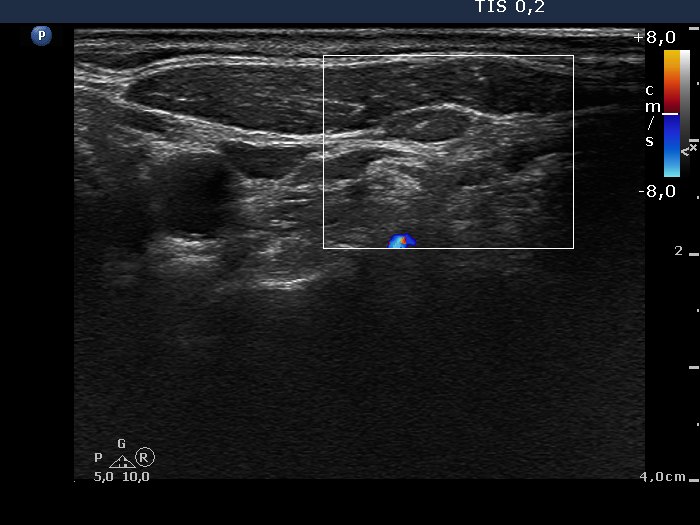

Lateral to the left lobe, transverse scan, color Doppler mode. The node is avascular.